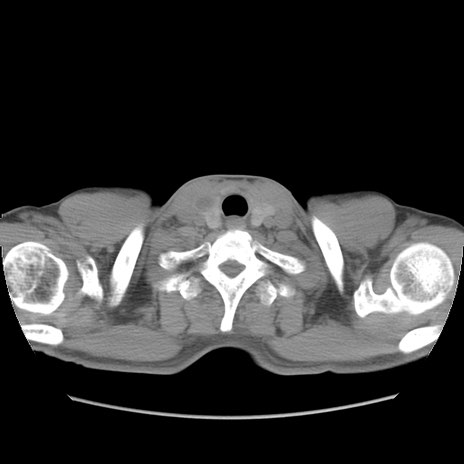

症例56 CT(横断像)

脂肪ウインドウ